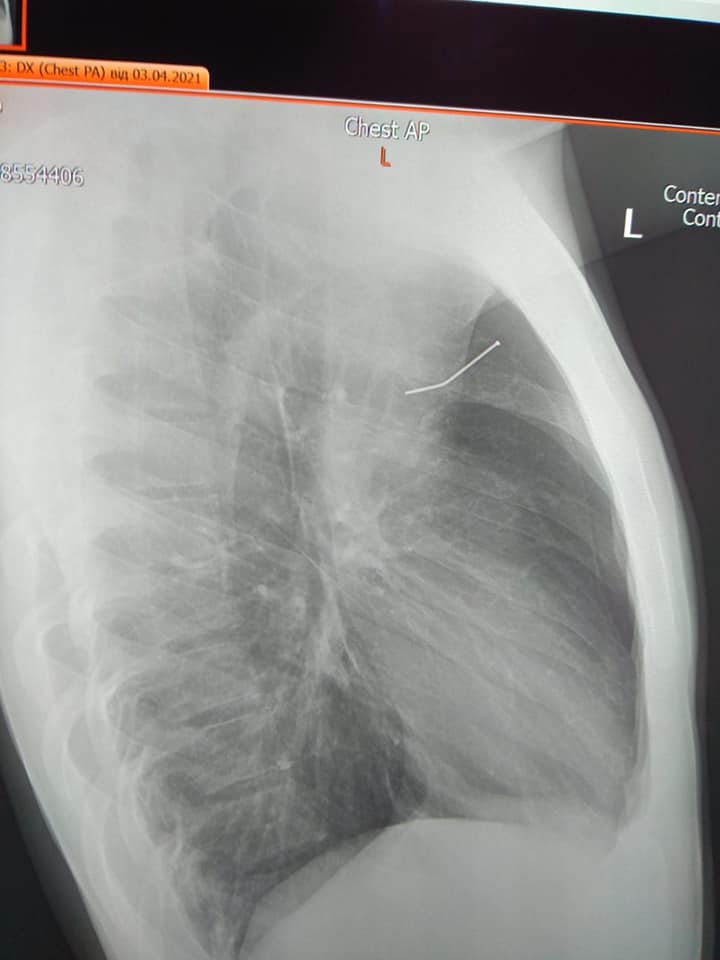

У молодого человека развился левосторонний пневмоторакс - воздух попал в грудную клетку, сдавило левое легкое и смещало сердце вправо. Парню сделали рентген и подозрение врачей оправдалось. У него был гвоздь в области левого легкого.

Во Львове врачи вытащили гвоздь из легкого подростка (фото: facebook.com/OHMATDYTLVIV)